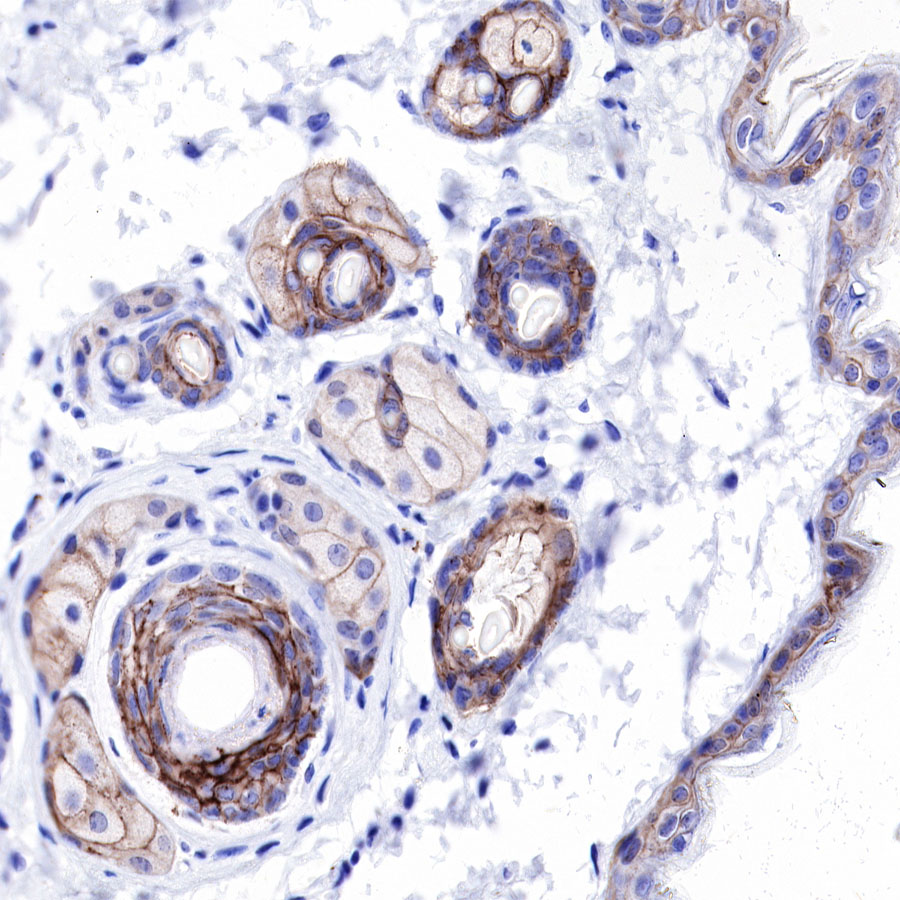

| IHC-P |

1:250 |

Claudin-1 is a protein that in humans is encoded by the CLDN1 gene.It belongs to the group of claudins.

Tight junctions represent one mode of cell-to-cell adhesion in epithelial or endothelial cell sheets, forming continuous seals around cells and serving as a physical barrier to prevent solutes and water from passing freely through the paracellular space. These junctions are composed of sets of continuous networking strands in the outwardly facing cytoplasmic leaflet, with complementary grooves in the inwardly facing extracytoplasmic leaflet. The protein encoded by this gene, a member of the claudin family, is an integral membrane protein and a component of tight junction strands. Loss of function mutations result in neonatal ichthyosis-sclerosing cholangitis syndrome.